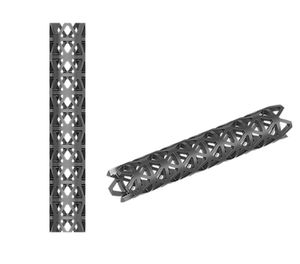

Prótesis para corpectomía vertebral

... - Material de aleación de titanio - Superficies superior e inferior dentadas para un agarre máximo - Diseño eficiente que proporciona un amplio espacio de injerto - Mecanismo de bloqueo de una etapa para evitar el desplazamiento - Implantación sencilla ...

... - Superficies superior e inferior dentadas para un agarre máximo - Diseño eficiente que proporciona un amplio espacio de injerto - Mecanismo de bloqueo de una etapa para evitar el desplazamiento - Implantación sencilla con un solo instrumento ...

... Sistema de jaulas CanMesh Categoría: Jaula de columna Productos personalizados ...

... Malla y cubierta de titanio SKU - Nombre T671 - Malla de titanio T672 - Cubierta de malla de titanio ...

... • Permitir un contacto completo con la superficie vertebral • Proporcionar una fijación segura con la característica de superficie roscada • Espacio de injerto eficiente antes de la distracción • Proporcionar un mecanismo de bloqueo ...

... Sistema toracolumbar distraible dual • Área inferior y superior angulada permiten un contacto completo con la superficie vertebral • Compuesto por una sola pieza • Proporciona una fijación segura con la característica de superficie ...